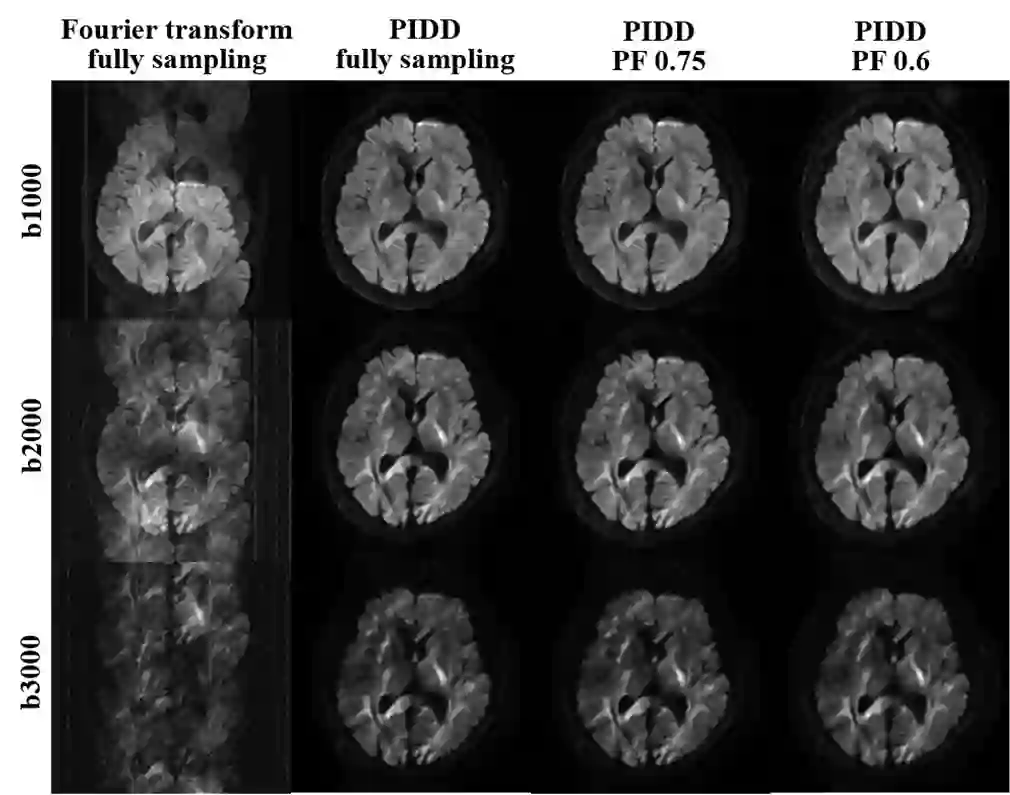

In this work, we propose a Physics-Informed Deep Diffusion magnetic resonance imaging (DWI) reconstruction method (PIDD). PIDD contains two main components: The multi-shot DWI data synthesis and a deep learning reconstruction network. For data synthesis, we first mathematically analyze the motion during the multi-shot data acquisition and approach it by a simplified physical motion model. The motion model inspires a polynomial model for motion-induced phase synthesis. Then, lots of synthetic phases are combined with a few real data to generate a large amount of training data. For reconstruction network, we exploit the smoothness property of each shot image phase as learnable convolution kernels in the k-space and complementary sparsity in the image domain. Results on both synthetic and in vivo brain data show that, the proposed PIDD trained on synthetic data enables sub-second ultra-fast, high-quality, and robust reconstruction with different b-values and undersampling patterns.